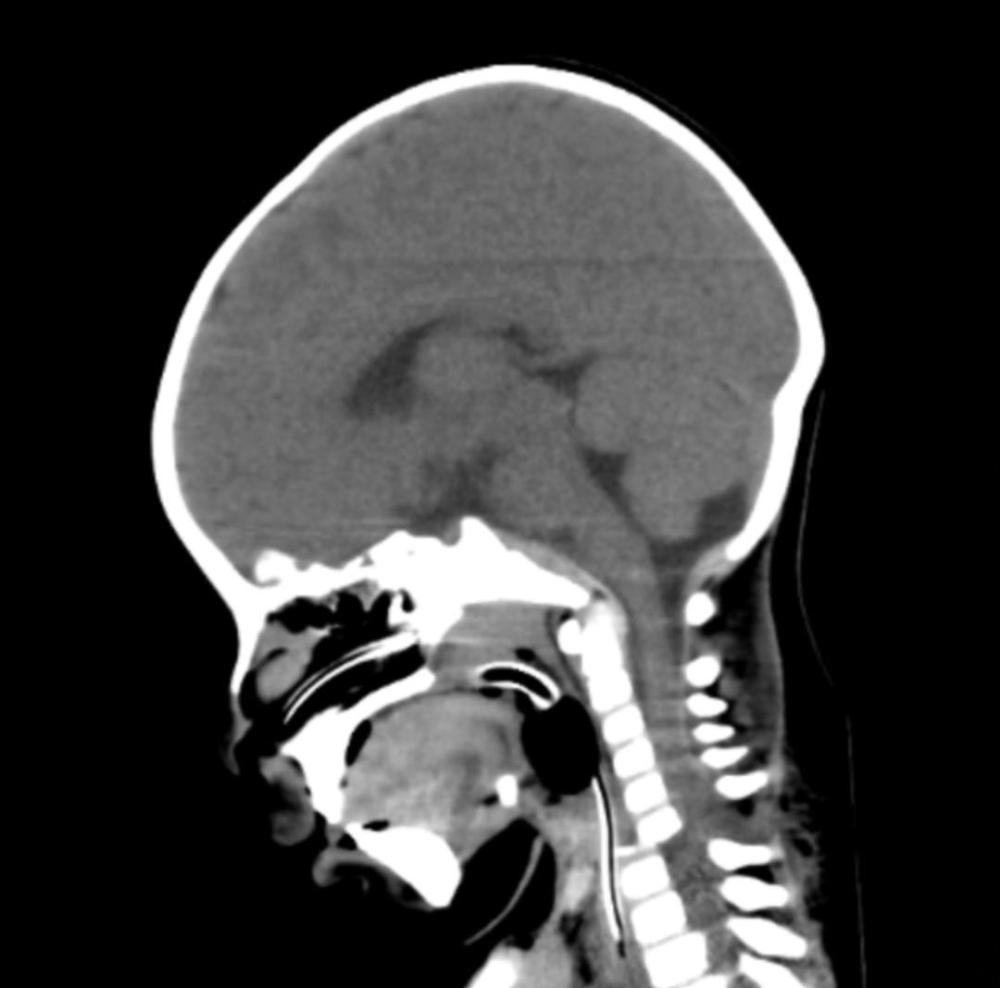

La vida de un bebé de seis meses, oriundo de la provincia de Jujuy, cambió drásticamente tras un grave accidente automovilístico. Producto del impacto, el pequeño sufrió politraumatismos severos, entre ellos una luxo fractura cervical causada por el cinturón de seguridad, cuadriparesia e inestabilidad hemodinámica. El pronóstico era reservado y la situación crítica.

Sin embargo, el Estado presente y la calidad del sistema de salud pública en Santiago del Estero permitieron dar una respuesta inmediata y de alto nivel: una cirugía de urgencia y alta complejidad que logró estabilizar su columna cervical, devolviéndole la movilidad y, con ello, la esperanza de una vida plena.